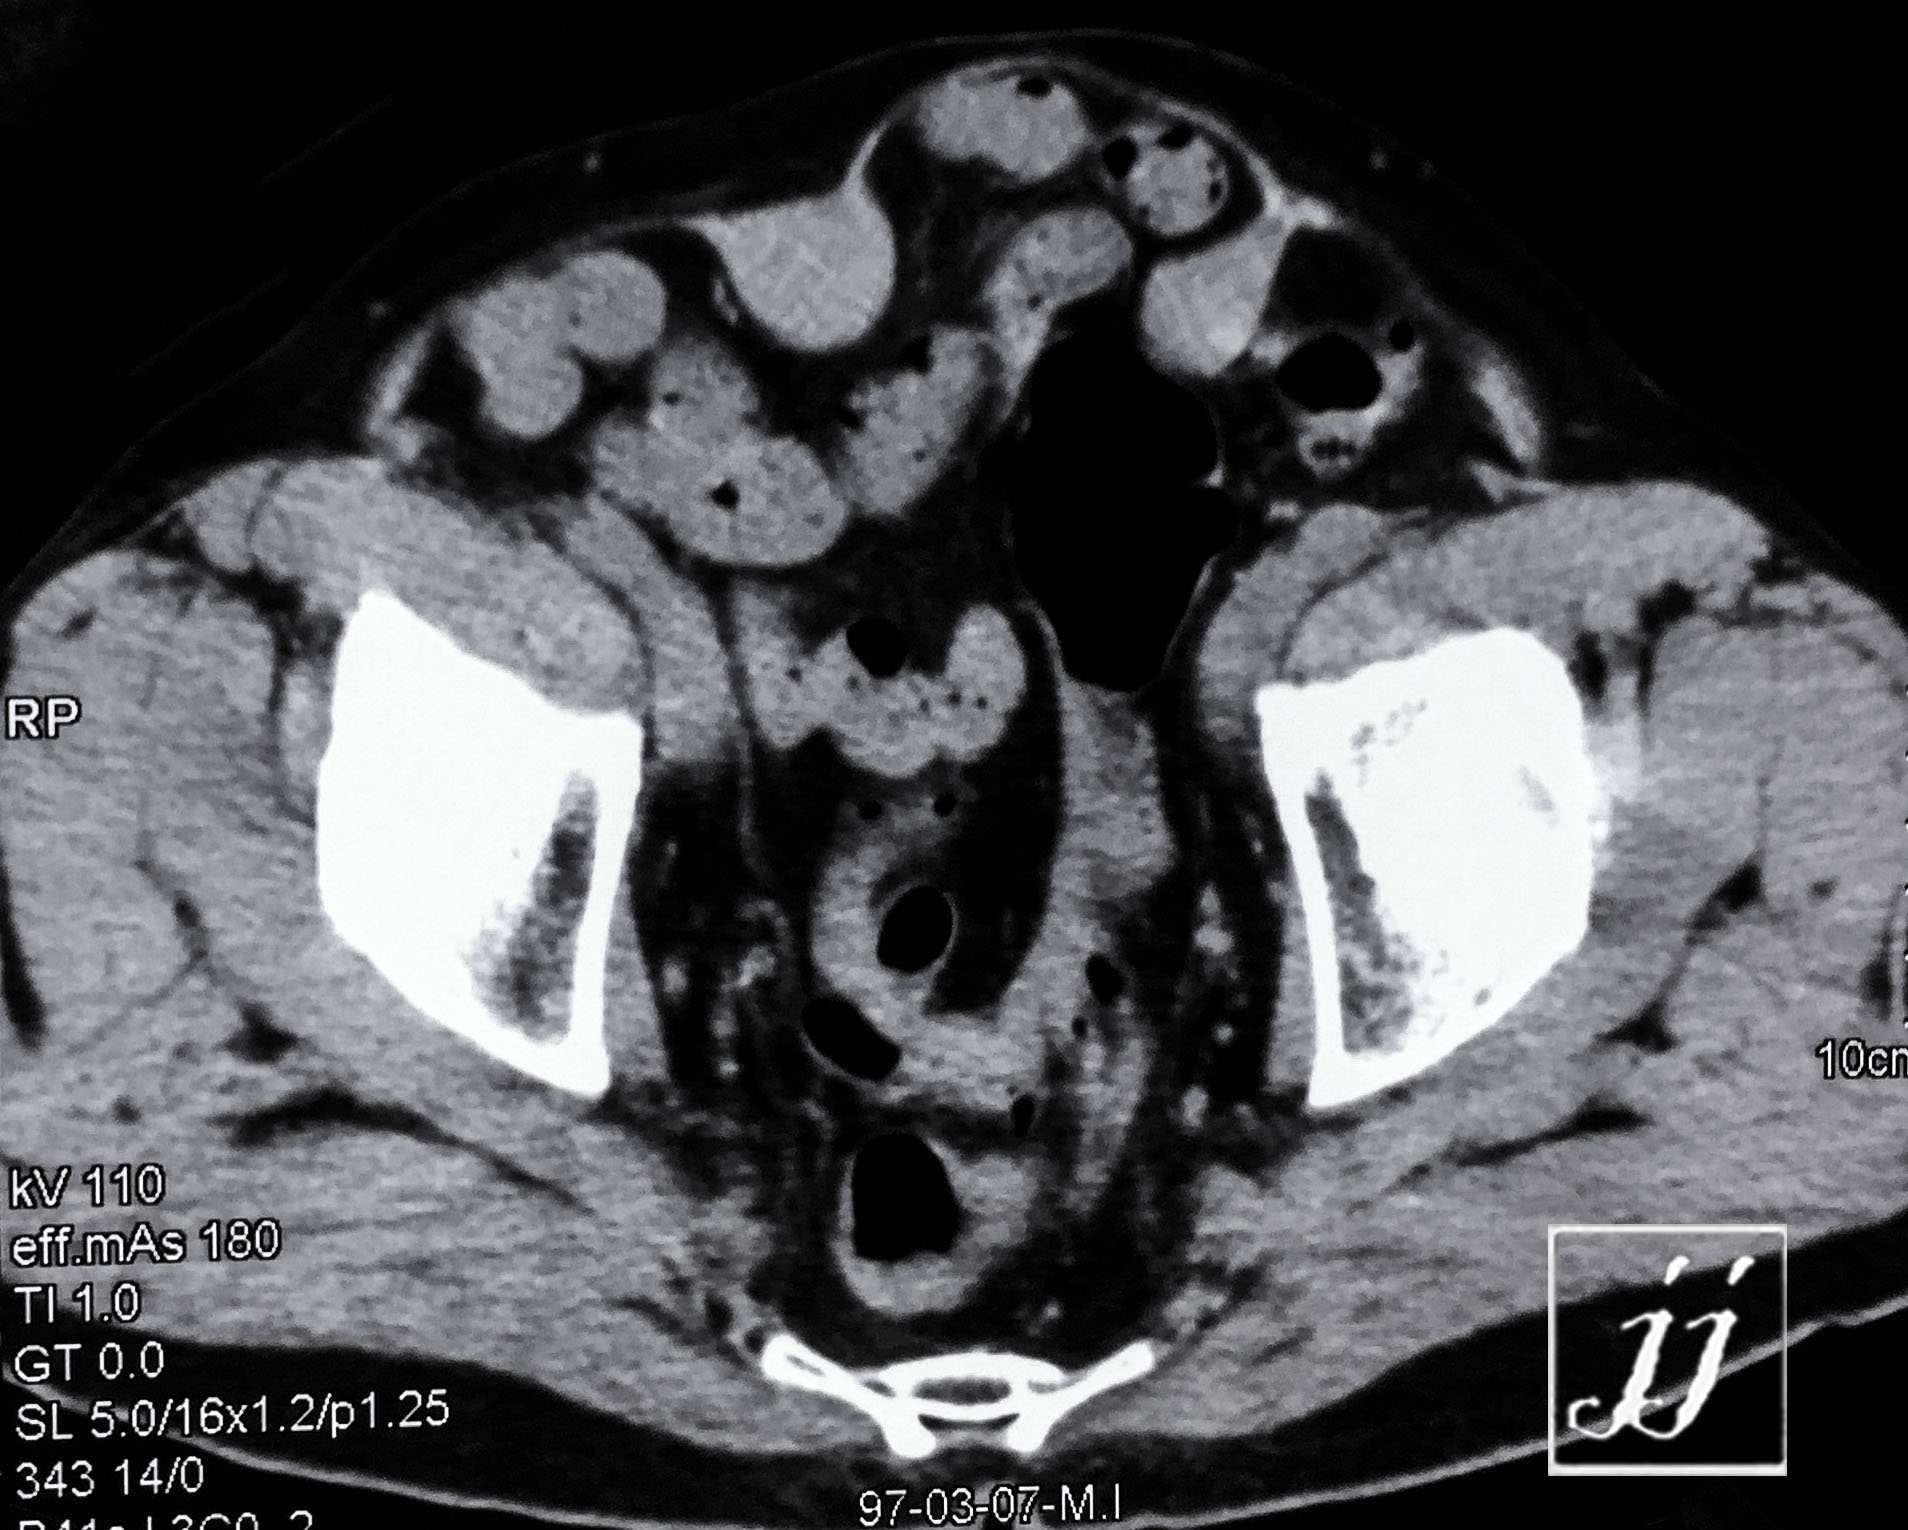

Abdomen- large left kidney cyst or tumor and inguinal hernia (4)